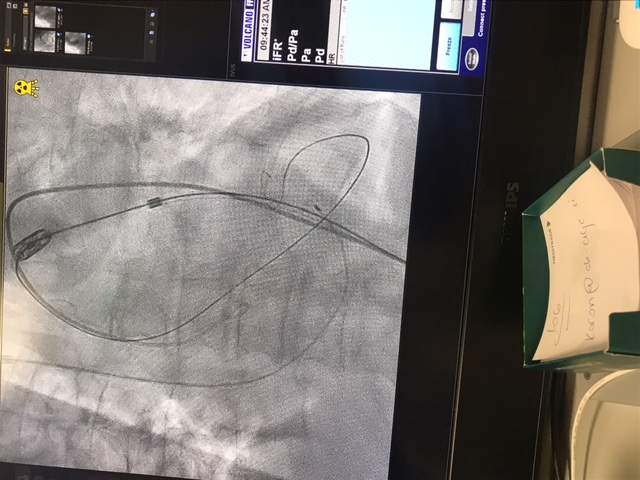

V Splošni bolnišnici Celje so prejšnji teden začeli izvajanje priznane klinične metode zdravljenja z zožitvijo aortne zaklopke – TAVI (Transcatheter Aortic Valve Implantation).

Prva posega so izvedli pod mentorstvom vodje katetrskega laboratorija UKC Ljubljana prof. dr. Matjaža Bunca in srčnega kirurga prim. Gorazda Koširja iz UKC Maribor. Bila sta uspešna, pacienta pa sta tri dni po posegu lahko zapustila bolnišnico.

Perkutana implantacija aortnih zaklopk (TAVI) ali vstavitev srčnih zaklopk skozi žilo na nogi je priznana klinična metoda zdravljenja bolnikov s pomembno zožitvijo aortne zaklopke.

Gre za poseg, pri katerem skozi eno od večjih arterij na stegnu uvedejo umetno biološko aortno zaklopko in jo po žilah vodijo do srca in mesta vstavitve. Njena bistvena prednost je minimalna invazivnost posega v telo. Drugi, kirurški načini namreč zahtevajo odprtje prsnega koša, zunajtelesni obtok in dolgotrajno splošno anestezijo.